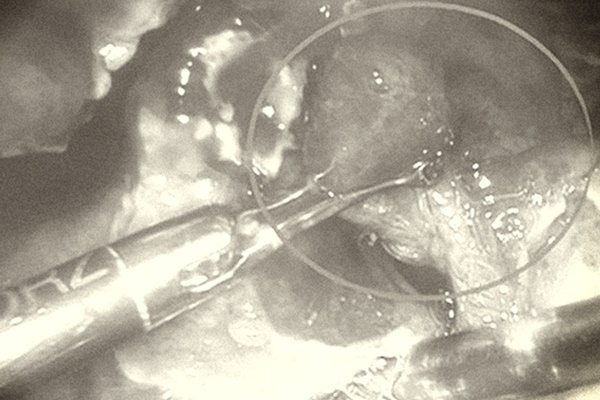

Sau khi tiếp nhận, thăm khám và làm các xét nghiệm, các bác sĩ xác định bệnh nhi bị viêm ruột thừa giai đoạn muộn, ruột thừa đã vỡ, gây viêm nhiễm lan tràn trong ổ bụng, phải mổ cấp cứu. Rất may mắn là các bác sĩ đã phẫu thuật được cho bệnh nhi bằng phương pháp nội soi, gỡ dính, cắt ruột thừa, hút rửa hết mủ trong ổ bụng.

Bệnh nhi được chẩn đoán viêm phúc mạc ruột thừa trong ổ bụng do ruột thừa đã vỡ, dịch mủ toàn bộ ổ bụng, được tiến hành phẫu thuật cấp cứu nội soi cắt ruột thừa viêm, rửa sạch ổ bụng, đặt dẫn lưu ổ bụng.